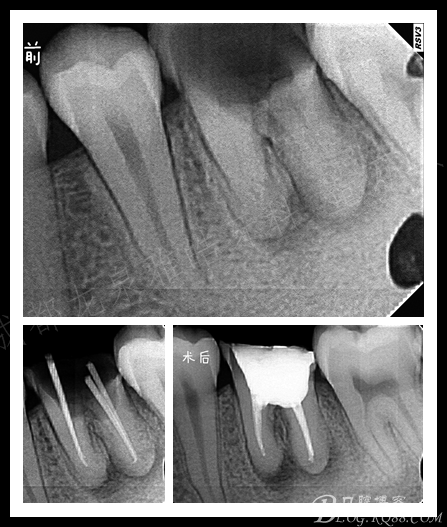

一个年轻人 应该是第3次治疗 了,上个就诊医生诊断是根管钙化不通,根管无法下去。

去除暂封,大家也看到了 ,开随孔决定了根管治疗的难易。

揭髓室顶 清理髓腔

8号 10号 15号 挫只疏通根管上段 预约时间预备根管中下段

其实这个是病例做的相对上2个 算是非常容易了 ,预弯疏通,预备 荡洗 充填。 耗时1个小时完成。

预备用的S3 我感觉很好用

牙髓炎 沟通的刚开始不是很顺利

主要是患者家属 抵触牙科 说我们牙科暴利呵呵

治疗方案 根管治疗+瓷嵌体修复

难点在于颊侧边缘的处理 ,是否需要切龈?

局麻下 去腐

开髓 去腐上了排龈线 看到边缘基本平龈 很清晰

第一次 封了失火剂 预约下次直接预备根充

张口度非常好 操作起来也是相当给力 给这个患者朋友32个赞

瓷嵌体修复完成后 除了 形态上的差异 其它做为我 还是觉得此病例是比较成功的

再治疗的

跟前几个病例一样的问题 髓室顶没有完全揭开(这个是我稍加调磨后的口内片)

建立直线通道 预备荡洗 根充 有了良好的视野,预备充填肯定是水到渠成。

术后 瓷嵌体修复